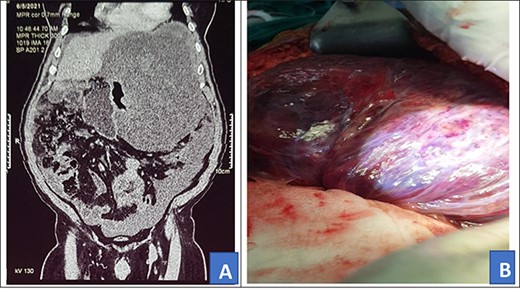

A 72-year-old African male presented with 10-month history of abdominal mass associated with early satiety, epigastric discomfort and weight loss. He had no history of any chronic illness and had a vague memory of his father’s grandmother being diagnosed with possible nasopharyngeal carcinoma and his uncle had radiotherapy for unknown brain tumor. On examination, he had a grossly distended abdomen with a firm mass in the left upper quadrant which was mildly tender. Other examination findings were unremarkable. Abdominal computed tomography (CT) scan done prior to admission showed a giant solid retro gastric mass involving part of the greater curvature of the stomach, spleen and part of the distal one-third of the transverse colon (Fig. 1A). The patient was scheduled for open surgery.

Contrasted abdominal CT scan (A) and intra-operative picture (B) for Patient 1.

Intra-operatively, a giant left upper quadrant tumor was found to be infiltrating and involving the spleen, greater curvature of the stomach and transverse colon (Fig. 1B). The tumor was mobilized from its retroperitoneal attachment, the splenic vessels were ligated and the entire tumor removed. Partial gastrectomy was done for the involved part and a 20-cm long distal transverse colectomy was done and a double barrel colostomy fashioned. The patient lost 1500 ml of blood and was transfused with two units of whole blood intra-operatively. The tumor was taken for histology and the results showed atypical pleomorphic spindle-shaped cells with abnormal mitosis. Immunohistochemistry: cells were positive for CD34 and CKIT which is in keeping with gastrointestinal stromal tumor.